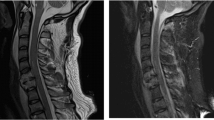

A 39-year-old man sustained a T8 spinal cord injury (SCI) in a motor vehicle accident in November 1999. He presented with a complete loss of sensorimotor function below T8. At the time of the injury, he received emergency treatment and standard rehabilitation followed by additional locomotor training. The patient was referred to our hospital in April 2009. After nearly 10 years of gait and standing training with long leg braces, he had no contraction of the leg muscles or anal sphincter and no sensation below T8. His neurological deficit was American Spinal Injury Association (ASIA) Impairment Scale (AIS) A. There was no EMG response in the leg muscles during leg-upward tasks, and transcranial motor evoked potential (MEP) elicited no leg muscle response. Magnetic resonance imaging showed an injured cord segment of 2.94 cm long with myelomalacia and atrophy (Figures 1a and b). The patient was scheduled for olfactory mucosa autograft (OMA) transplantation to the injury site. He underwent intensive in-hospital rehabilitation for 2 months before transplantation, during which his neurological deficit did not improve. The rehabilitation schedule is shown in Table 1.

Magnetic resonance imaging (MRI). (a) T1-weighted sagittal image before transplantation shows atrophic change of the thoracic spinal cord. (b) T2-weighted sagittal image before transplantation shows an intramedullary high-intensity area. MRI at 48 weeks after transplantation shows fairly complete filling of cavities with heterogeneous intensity on T1- (c) and T2-weighted (d) images. (e) Gadolinium-enhanced images also show heterogeneous enhancement of the grafts. No evidence of neoplastic tissue overgrowth was observed during the initial follow-up period.

In terms of the SCI, magnetic resonance imaging at 48 weeks after OMA showed fairly complete filling of cavities with heterogeneous signal intensities on T1- and T2-weighted images. Gadolinium-enhanced magnetic resonance imaging also showed heterogeneous enhancement of the graft. No evidence of neoplastic tissue overgrowth was observed (Figures 1c–e).